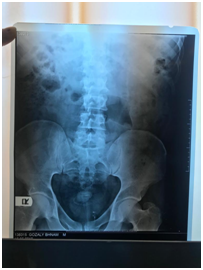

A 40 years’ man with a history of nephrolithiasis referred for LUTS and bladder stone in evaluation of bladder stone it was discovered that there is a. stent in urinary system of left kidney (Figure 1). The patient was candidate for ESWL after once time ESWL he was carried out for cystoscopy to removing stent and remained of bladder stone. In cystoscopy with covering of antibiotic nelatone of ureter easily removed which was intact (Figure 2) and also the remained of bladder stone.

Figure 1 KUB: nelatone with left kidney.